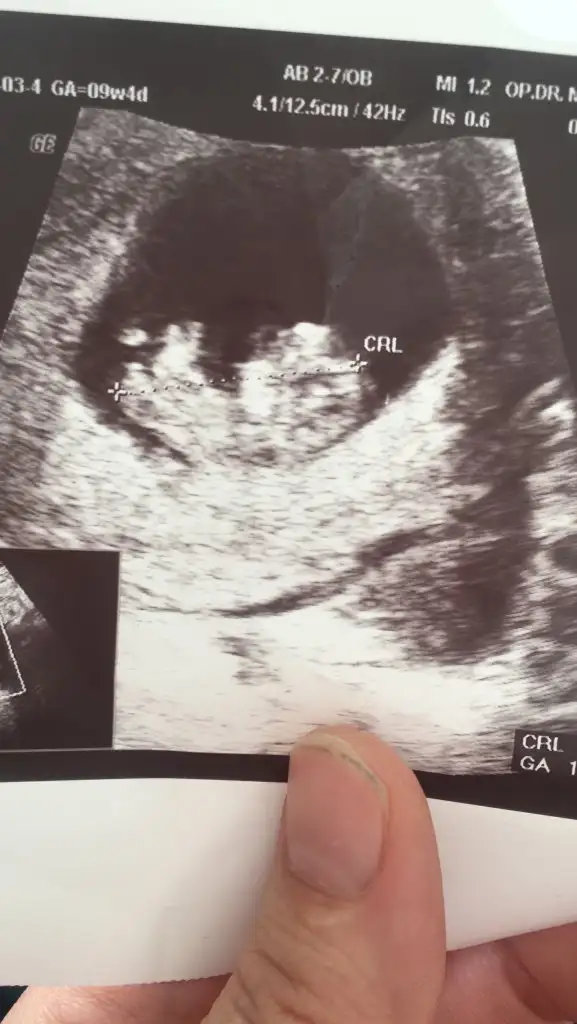

Merhaba banada tahminde bulunur musunuz ilk resim 13 hafta ikinci resim 11 hafta